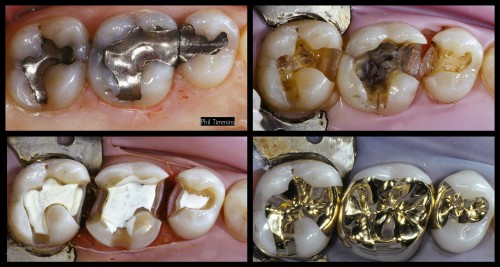

Gold Phil Timmins

If you ever get an opportunity to work with Tucker gold people, take it….because they […]